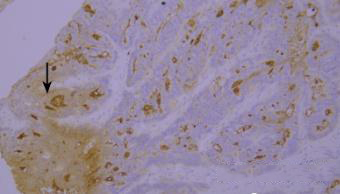

染色液的堆积(黑色箭头区域)。

优化建议:

充分洗涤。